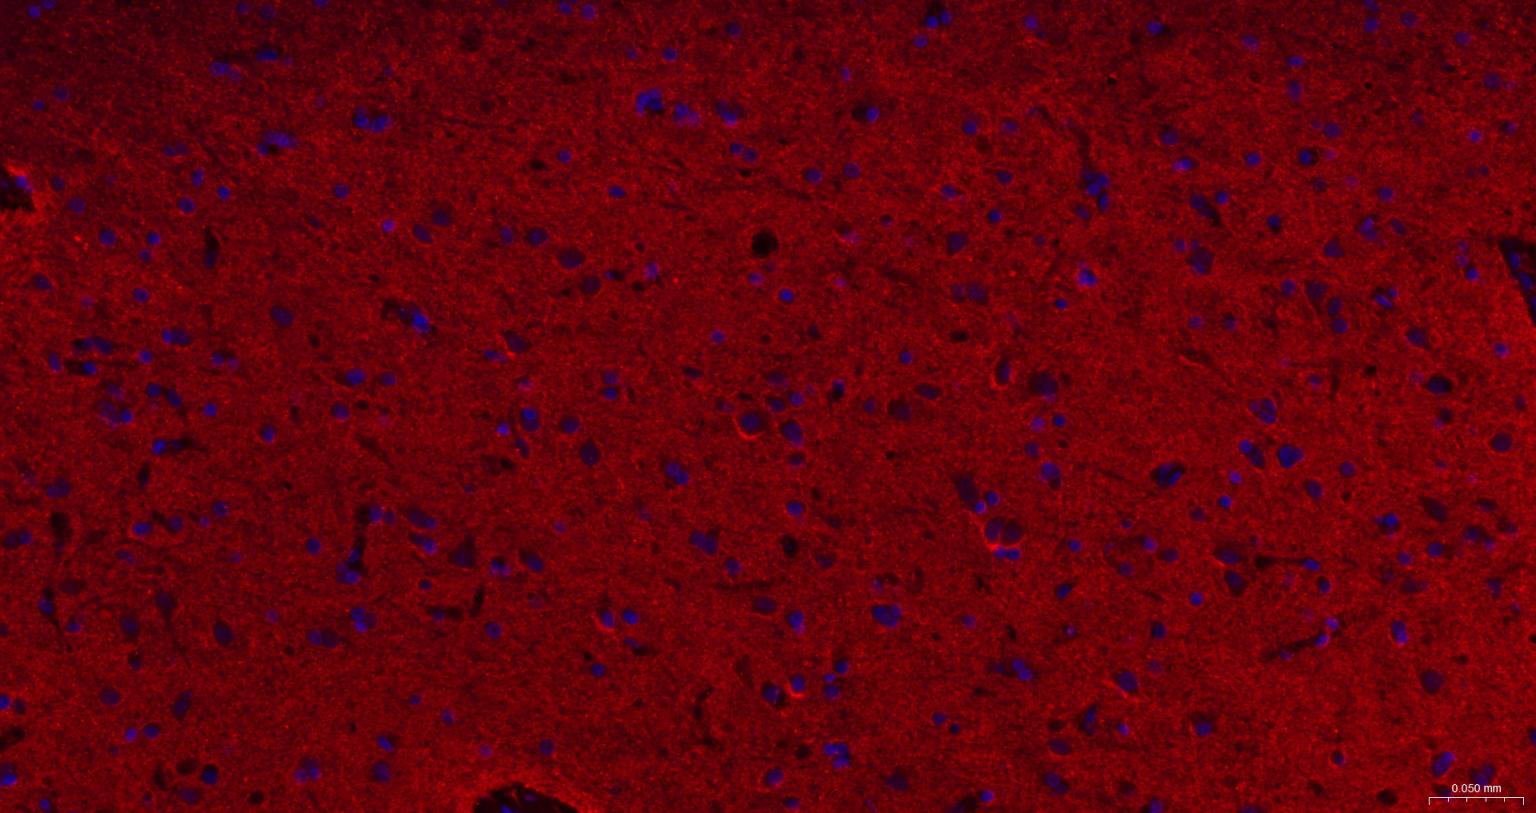

Paraformaldehyde-fixed, paraffin embedded Human Cerebrum; Antigen retrieval by boiling in sodium citrate buffer (pH6.0) for 15 min; The section was incubated with Alpha Synuclein Monoclonal Antibody, Unconjugated (bsm-54277R) at 1:200 overnight at 4°C. Followed by conjugated Goat Anti-Rabbit IgG antibody (Red, bs-0295G-BF594), DAPI (blue, C02-04002) was used to stain the cell nuclei.